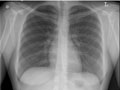

- Do a chest X-ray to look at your lungs.

To find out if you have COPD, your doctor will do a physical exam, ask questions about your health, and may do blood tests. Your doctor may do a chest X-ray to look at your lungs and have you do breathing tests to find out how well your lungs work.